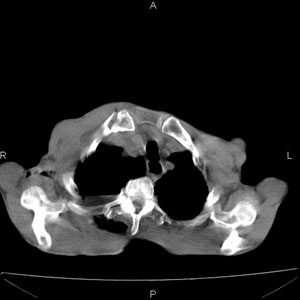

患者男,77岁,于3日前从树上摔下,头部查ct示蛛血,硬膜下出血,上腹部ct未见明显异常,右侧胸腔积液,左侧如常。肺部拍片示右侧肋骨多发骨折住院后今日来查肺部ct,我看到的是1。右侧胸腔血气胸并右肺上叶,中叶压缩性肺不张,2。右肺下叶肺挫伤并多发肋骨骨折,肌内及皮下积气3。左侧少量胸腔积液,我想请教的是3天前左侧胸腔里没有积液今天怎么出现了呢,是什么原因呢?请讨论。

右侧多发肋骨骨折,同侧液气胸